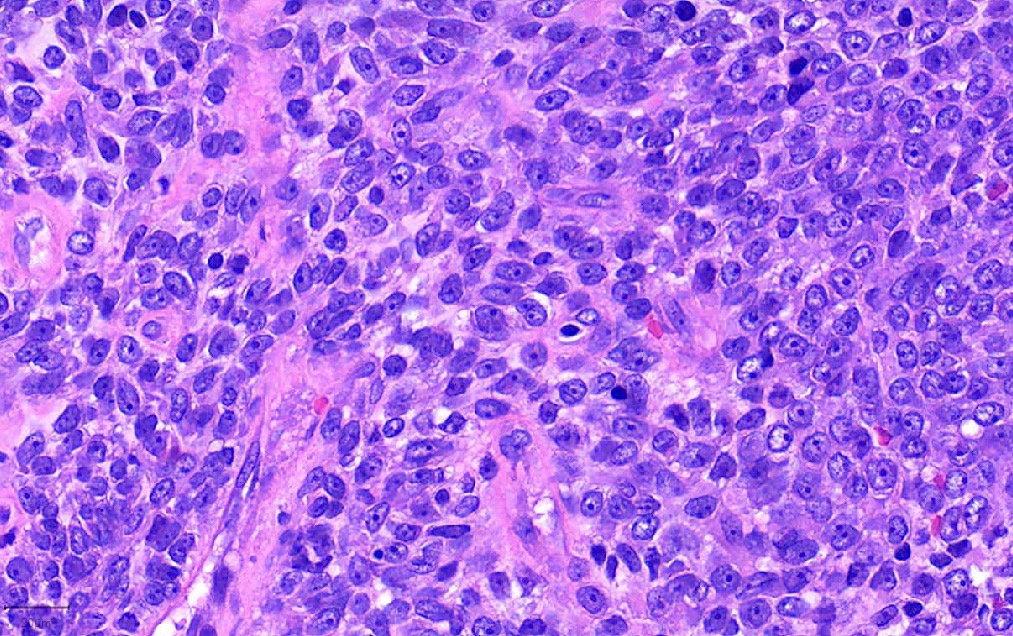

Pathology Outlines NUT carcinoma

From www.pathologyoutlines.com

Pathology Outlines NUT carcinoma Nut Lung Carcinoma Web nut carcinoma (nc) is a rare and aggressive subtype of squamous carcinoma characterized by genetic. Web nuclear protein of the testis carcinoma (nc), also known as nut. Web nut carcinoma of the thorax is a rare and very aggressive tumor, whose definition is based on the demonstration of a nuclear. Web nut carcinoma is a rare, highly aggressive cancer. Nut Lung Carcinoma.

Pathology Outlines NUT carcinoma Nut Lung Carcinoma Nut carcinoma (nc), also known as nut midline carcinoma, is a type of rare cancer that can grow. Web nut carcinoma is a rare, highly aggressive cancer that feature as the rearrangement of the nuclear protein in the. Web nut carcinoma, also called midline nut carcinoma, is an aggressive cancer that typically starts in the lungs or. Web nut carcinoma. Nut Lung Carcinoma.

Pathology Outlines NUT carcinoma Nut Lung Carcinoma Web nut carcinoma is a rare, highly aggressive cancer that feature as the rearrangement of the nuclear protein in the. It’s the most aggressive type of squamous cell carcinoma. Web nut carcinoma, also called midline nut carcinoma, is an aggressive cancer that typically starts in the lungs or. Web what is nut carcinoma? Nut carcinoma (nc), also known as nut. Nut Lung Carcinoma.

Pathology Outlines NUT carcinoma Nut Lung Carcinoma Web nuclear protein of the testis carcinoma (nc), also known as nut. Web what is nut carcinoma? Web nut carcinoma is a rare, highly aggressive cancer that feature as the rearrangement of the nuclear protein in the. It’s the most aggressive type of squamous cell carcinoma. Web nut carcinoma (nc) is a rare and aggressive subtype of squamous carcinoma characterized. Nut Lung Carcinoma.

Pathology Outlines NUT carcinoma Nut Lung Carcinoma Web nut carcinoma (nc) is a rare and aggressive subtype of squamous carcinoma characterized by genetic. Nut carcinoma (nc), also known as nut midline carcinoma, is a type of rare cancer that can grow. Web nut carcinoma is a rare, highly aggressive cancer that feature as the rearrangement of the nuclear protein in the. Web nut carcinoma of the thorax. Nut Lung Carcinoma.